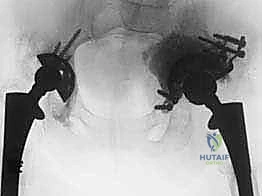

- الأشعة السينية (X-rays): صور متعددة الزوايا للحوض ومفصل الورك لتقييم وضع المفصل القديم، ومقدار هجرته، وعلامات تحلل العظم.

- الأشعة المقطعية ثلاثية الأبعاد (3D CT Scan): هذا هو الفحص الأهم على الإطلاق للتخطيط لجراحة القفص. يوفر صورة مجسمة دقيقة توضح حجم العيب العظمي، ومكان العظم السليم المتبقي الذي سيتم تثبيت مسامير القفص فيه.

| وجه المقارنة | استبدال مفصل الورك الأولي (Primary THA) | مراجعة مفصل الورك بالقفص (Revision with Cage) |

|---|---|---|

| السبب الرئيسي | خشونة المفاصل، التهاب المفاصل الروماتويدي | فشل المفصل السابق، تآكل وفقدان عظمي هائل |

| حالة العظم | العظم الحقي (الحوض) سليم وقادر على الدعم | عظم الحوض متآكل، مدمر، أو به فجوات كبيرة |

| نوع الغرسات (المفصل) | كوب معدني قياسي يُثبت بالضغط أو الأسمنت | قفص معدني كبير بحواف طويلة + براغي متعددة + كوب أسمنتي |